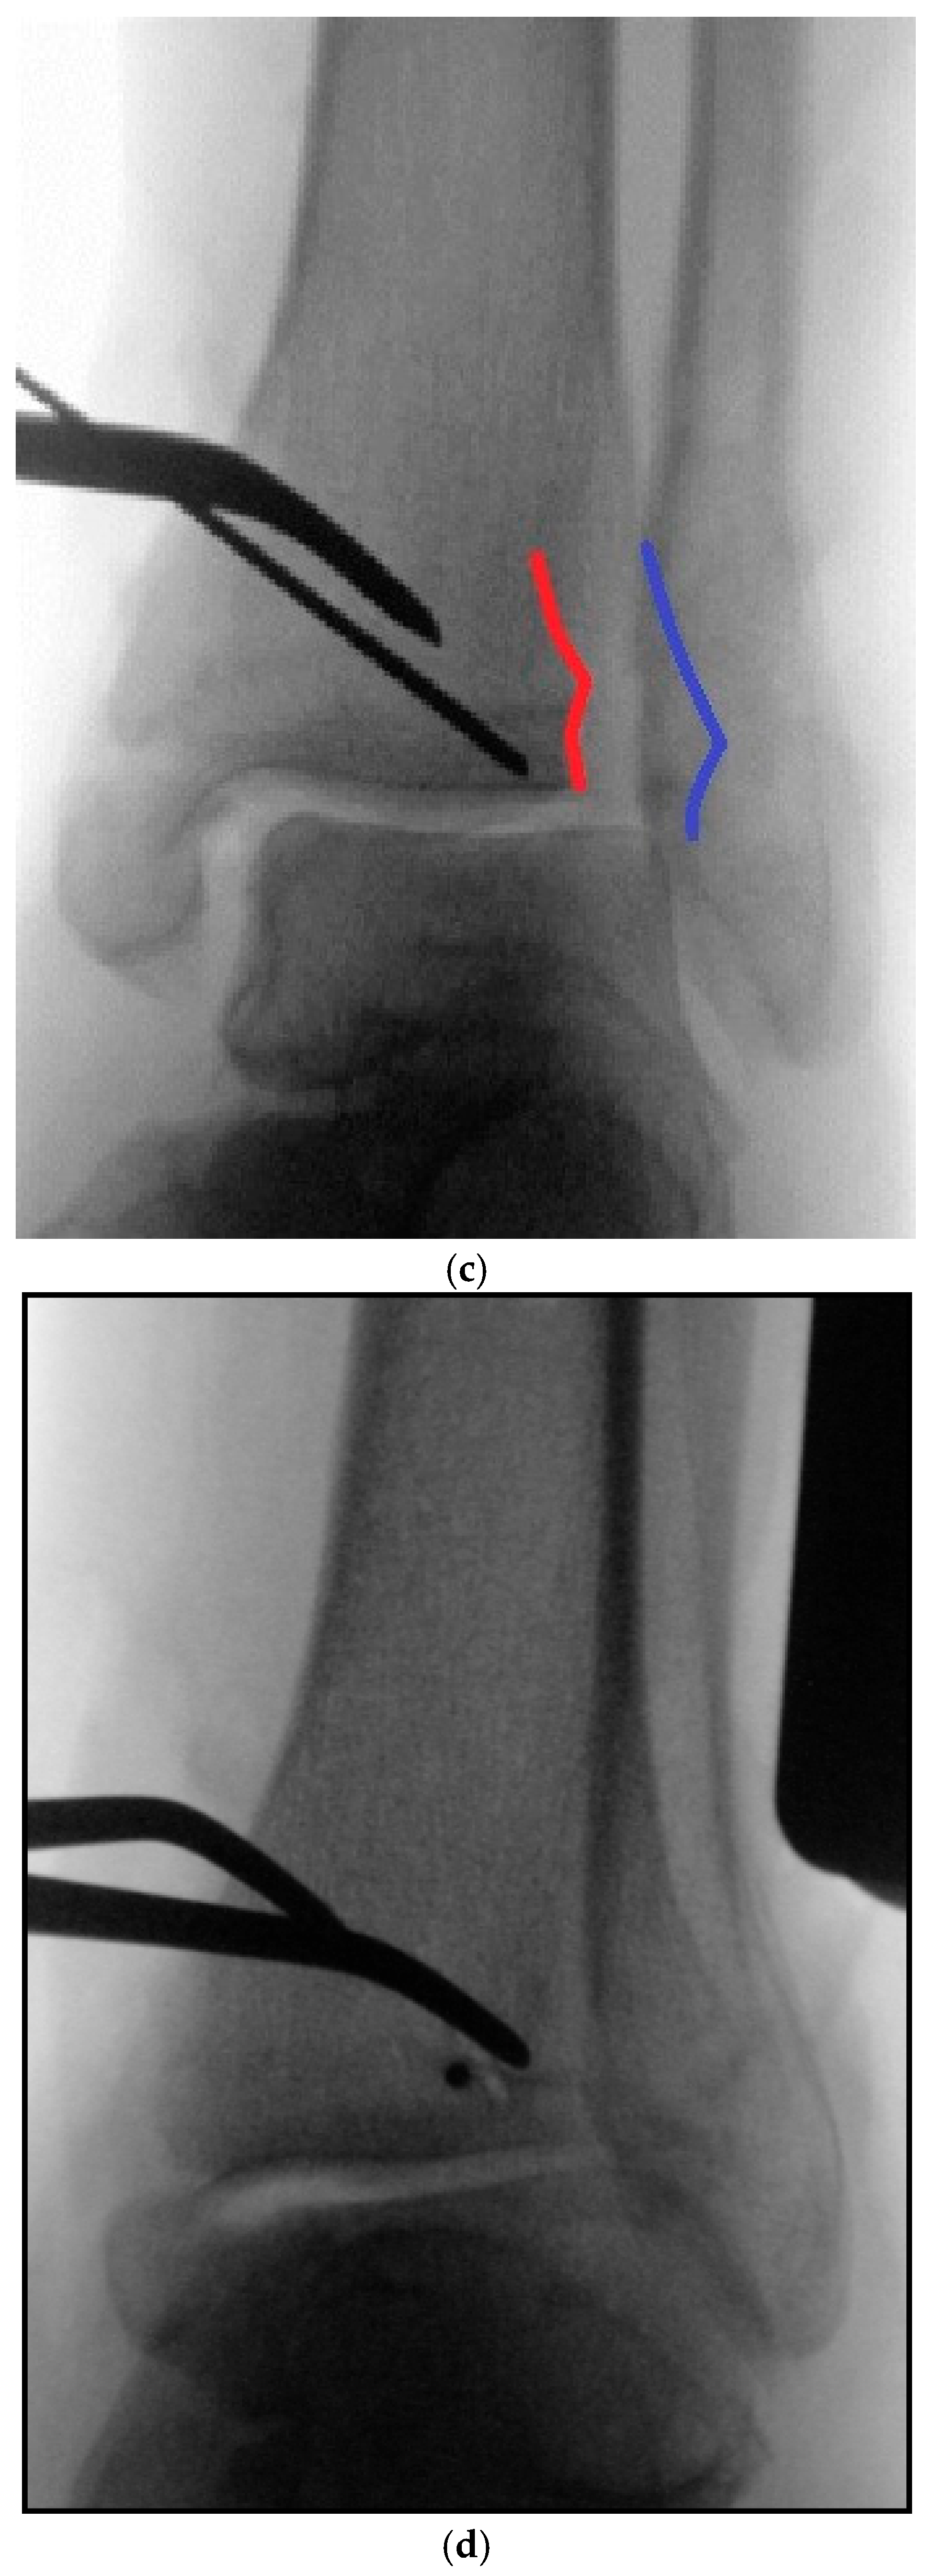

3. Intraoperative 3D Fluoroscopic Control

5.1. Surgical Considerations

5.2. Inside-Out Fixation of the Posterior Malleolus Using a Headless Double-Threaded Compression Screw